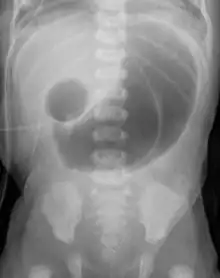

| Radiograph with double bubble sign indicating duodenal atresia | |

If not diagnosed in utero, infants with intestinal atresia are typically diagnosed at day 1 or day 2 after presenting with eating problems, vomiting, and/or failure to have a bowel movement.[3] Diagnosis can be confirmed with an X-ray, and typically followed with an upper gastrointestinal series, lower gastrointestinal series, and ultrasound.[5][3]

- Duodenal atresia – malformation of the duodenum, part of the intestine that empties from the stomach, and first section of the small intestine